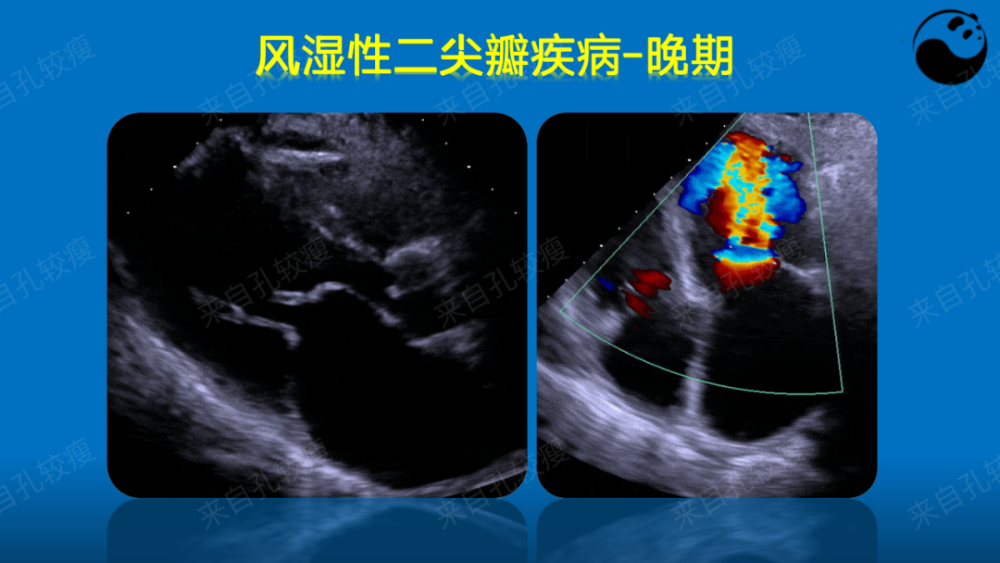

开放受限样前后瓣同向运动二尖瓣前 叶活动曲 线因ef 斜率减慢 双峰